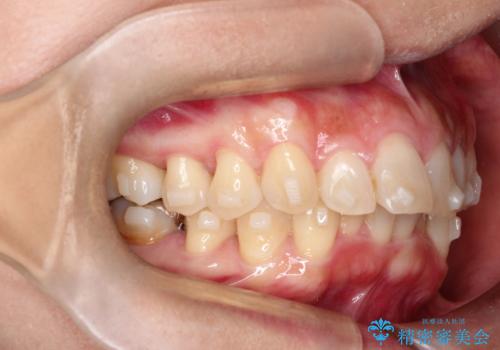

- 前歯の凸凹を主訴に来院されました。

臼歯部の遠心移動を行いながらスペースを作り、インビザラインにて前歯をきれいに並べることができました。

今回の治療計画では臼歯部の遠心移動とIPRを行っています。